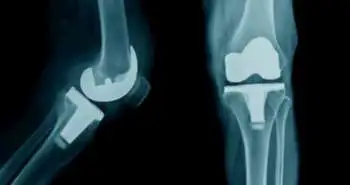

Intravenous acetaminophen as an adjunct to multimodal analgesia after total knee and hip arthroplasty: A systematic review and meta-analysis

To examine the influence of additional intravenous Acetaminophen to manage pain appear after the total joint arthroplasty (TJA).

Pain control after the major orthopedic surgery has become a serious clinical problem. Although numerous analgesic methods have been applied, they have not provided sufficient relief from the pain. Therefore Liqing Yang et al performed a meta-analysis and reported that intravenous acetaminophen to multimodal analgesia could significantly reduce pain.

Four studies comprising 865 participants were selected for the analysis. The meta-analysis revealed significant differences between groups regarding pain scores and opioid consumption at POD 1, POD 2, and POD 3.

Additional intravenous Acetaminophen to multimodal analgesia could considerably lessen the pain and opioid intake following total joint arthroplasty with fewer adverse events. Greater quality RCTs are needed for more research.